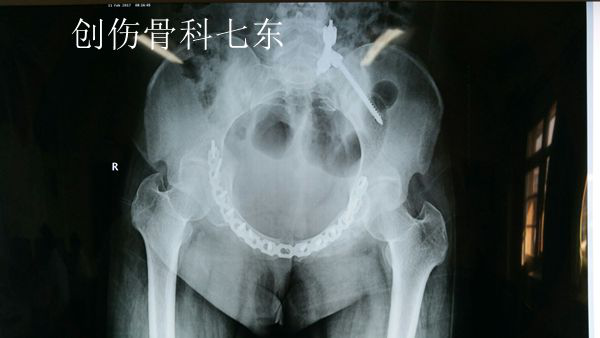

骨盆入口位可见骨折得到满意复位,内植物位置满意,固定稳固

骨盆出口位可见骨折得到满意复位,内植物位置满意,固定稳固

患者术前射片见骨盆C型骨折,前后环均受累,严重影响稳定性,需要手术治疗复位骨折并恢复骨盆环稳定性。为了进一步评估骨折情况,创伤骨科七东专家团队对患者进行了CT三维重建检查。考虑到患者骨盆前环需要复位并需要跨双侧髋臼前方的钢板固定,内植物长度跨越范围大,骨盆解剖形态复杂,并可能涉及周围重要神经血管结构,医生借助时下最为前沿的3D打印技,对患者骨盆进行等比例复制,以进行更周密的术前计划和准备。